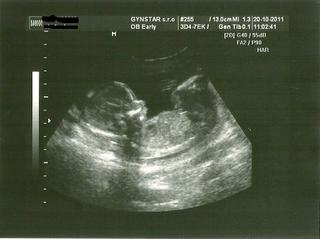

Babyyyyyy idem z toho ultrazvuku 😵 vyzerá to, že je všetko maximálne v poriadku, dr. mi ukázala každú časť telíčka a povedala, že keby nevedela o mojom karyotype ani by ma na amnio neodporučila 😵 veľmi sa tešííím a som šťastná prešťastná 😵

@atreyu aký je náááááádherný. Juj až slzička mi vyšla. Som šťastnááá že je všetko v poriadku. Naozaj modlila som sa za teba. No stráááášne sa teším. A teším sa aj tomu že sóda sklamala......mne tiež nepení, tak dúfam že aj ja budem mať chlapiska. BLAHOŽELÁAAAAAAAAAAAAAAAAAAAAAAAAAAAAAAAAAAM!!!!!!!! 🙂